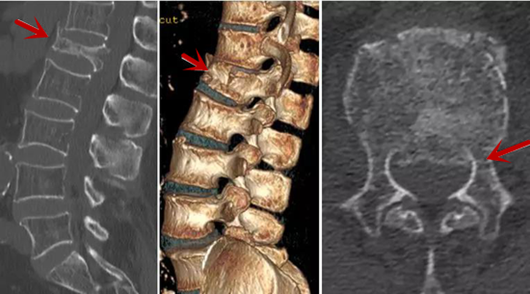

CT利用X射線對人體檢查部位通過電腦切成若干層掃描,然后把每層的圖像都能顯示出來。CT相對于X光片具有更高的密度分辨力,可直接顯示X線片無法顯示的病變,觀察腰椎有無微小的骨折、骨質(zhì)有無破壞等骨質(zhì)情況、以及腰椎間盤突出、腰椎神經(jīng)根、椎管、椎間小關(guān)節(jié)的情況等。同時還可以通過后處理,重建腰椎矢狀位或冠狀位圖像,形成腰椎的3D圖像,更直觀地觀察病變部位,對腰椎手術(shù)風(fēng)險具有提示作用,對手術(shù)方式的選擇具有指導(dǎo)意義,但是對神經(jīng)、脊髓損傷程度的顯示不如MRI,軟組織的分辨率仍有一定限制,對椎管內(nèi)病變顯示欠佳,且有一定的輻射。

從左向右依次為CT矢狀位重建圖像、三維重建圖像、軸位掃描圖像,箭頭提示腰1椎體爆裂性骨折